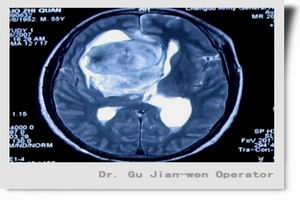

顱咽管癌是一種良性先天性腫瘤,從胚胎期顱咽管的殘餘組織發生。發病率顱咽管瘤約占顱內腫瘤的4%。但在兒童卻是最常見的先天性腫瘤,占鞍區腫瘤的第一位。本病可以發生在任何年齡,但70%是發生在15歲以下的兒童和少年。顱咽管瘤亦稱垂體管瘤,是胚胎期顱咽管的殘餘組織發生的良性先天性腫瘤,約占顱內腫瘤的4%,占鞍區腫瘤的第一位,發病高峰為15歲或13歲,女性稍多於男性。

顱咽管癌可見於任何年齡,但以6~14歲最多見,初發時為良性腫瘤,大多數顱咽管瘤呈間歇性生長,故總體上看腫瘤生長較慢,其症狀發展也慢;少數顱咽管瘤生長快速,其病情進展亦較快。其臨床表現包括以下幾個方面:腫瘤占位效應及阻塞室間孔引起的高顱壓表現;腫瘤壓迫視交叉、視神經引起的視力障礙;腫瘤壓迫下丘腦、垂體引起的下丘腦-垂體功能障礙;腫瘤侵及其他腦組織引起的神經、精神症狀,有以下幾點: